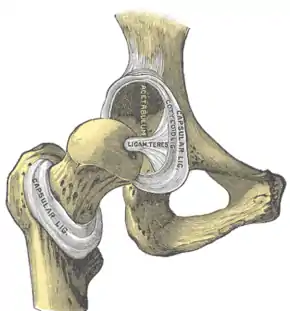

The cuplike acetabulum forms at the union of three pelvic bones — the ilium, pubis, and ischium.[6] The Y-shaped growth plate that separates them, the triradiate cartilage, is fused definitively at ages 14–16.[7] It is a special type of spheroidal or ball and socket joint where the roughly spherical femoral head is largely contained within the acetabulum and has an average radius of curvature of 2.5 cm.[8] The acetabulum grasps almost half the femoral ball, a grip deepened by a ring-shaped fibrocartilaginous lip, the acetabular labrum, which extends the joint beyond the equator.[6] The centre of the acetabulum (fovea) does not articulate to anything. Instead, it is lined with fat pad and attached to ligamentum teres. The acetabular labrum is horse-shoe shaped. Its inferior notch is bridged by transverse acetabular ligament.[5] The joint space between the femoral head and the superior acetabulum is normally between 2 and 7 mm.[9]

The intracapsular ligament, the ligamentum teres, is attached to a depression in the acetabulum (the acetabular notch) and a depression on the femoral head (the fovea of the head). It is only stretched when the hip is dislocated, and may then prevent further displacement.[22] It is not that important as a ligament but can often be vitally important as a conduit of a small artery to the head of the femur, that is, the foveal artery.[26] This artery is not present in everyone but can become the only blood supply to the bone in the head of the femur when the neck of the femur is fractured or disrupted by injury in childhood.[27]